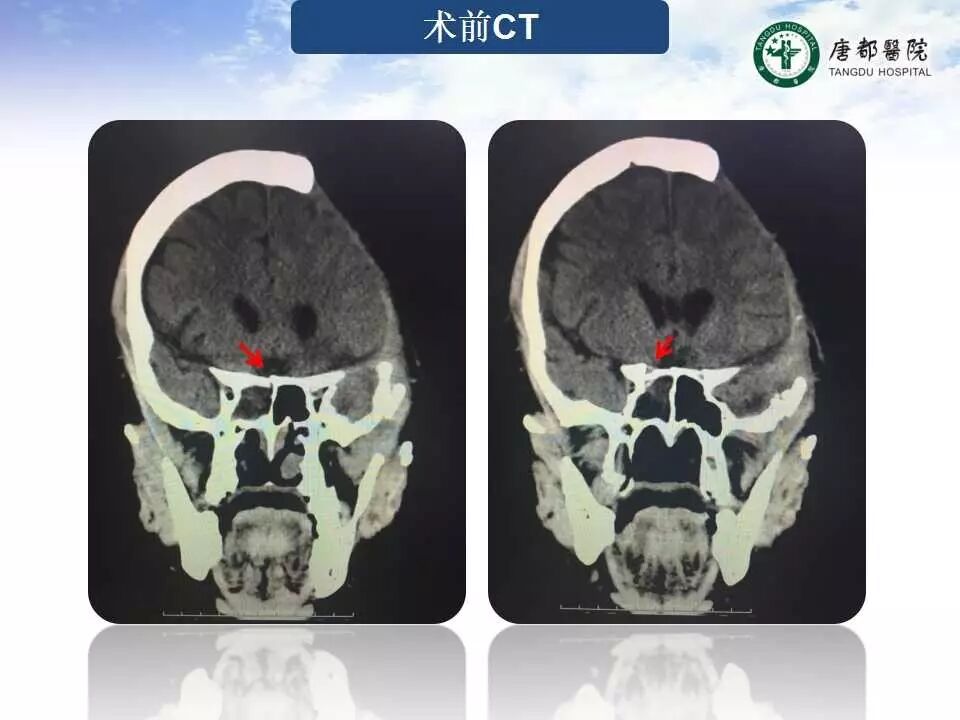

Case 2